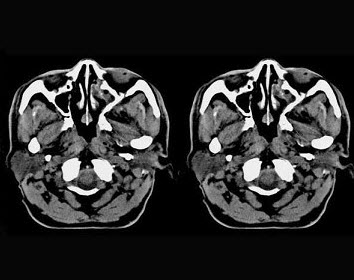

男,61岁,流鼻血三天。如图所示最可能的诊断为()。

A:鼻咽淋巴滤泡增生

B:鼻咽腺样体增生

C:鼻咽纤维血管瘤

D:小唾液腺瘤

E:鼻咽部息肉